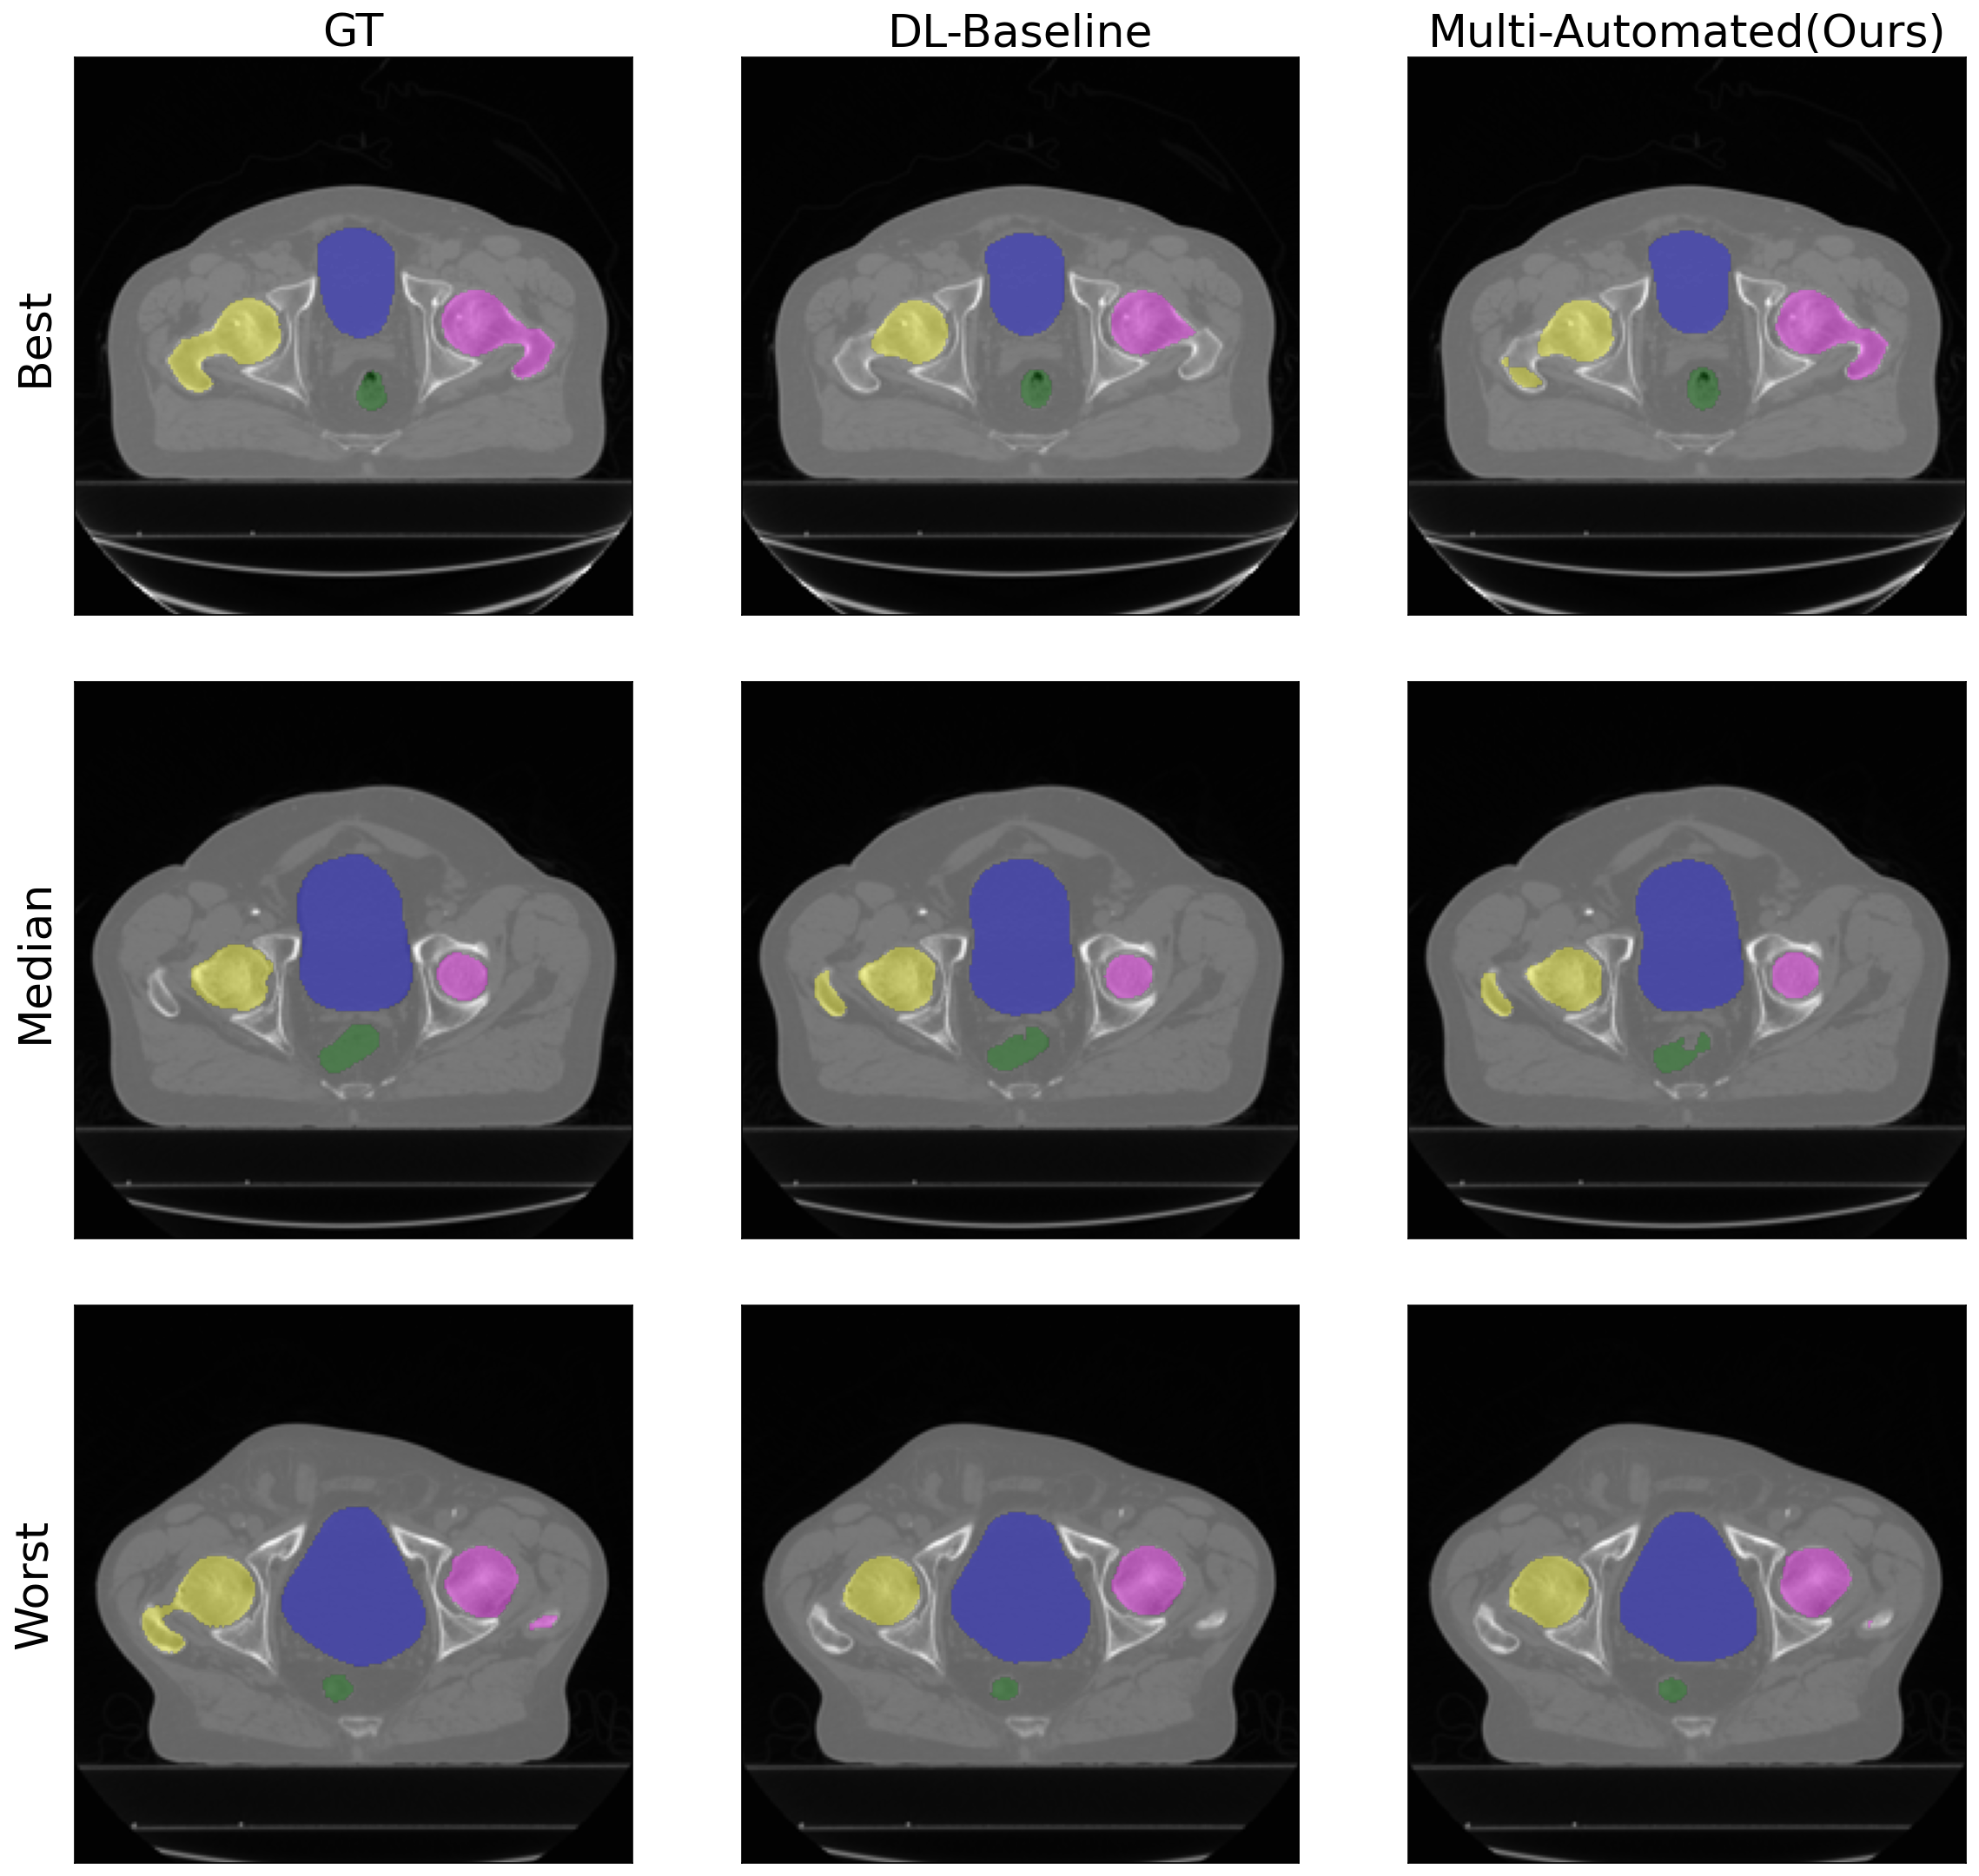

Additionally, results in Table 4 and Table 5 show that Multi-Automated achieves comparable performance in contouring when trained for dose prediction simultaneously. The Dice Score Coefficients for the baseline single-task learning model for contouring are 0.818 and 0.674 for the prostate and OpenKBP datasets, respectively. In contrast, Multi-Automated achieves dice score coefficients of 0.824 and 0.716, respectively, showing better performance in OpenKBP datasets. For Hausdorff distance, compared to 7.549 and 39.831 in baseline, Multi-Automated results show 12.049 and 22.872 for Prostate and OpenKBP datasets, respectively. In Figure 3 and Figure 5, we further illustrate the qualitative results of both the baseline model and Multi-Automated for the prostate and OpenKBP datasets, respectively.

Table 4: Dice score coefficient and Hausdorff distance using Prostate dataset for baseline DL contouring model (DL-Baseline) and the automated contouring and planning model using multi-task learning (Multi-Automated). Better results for each ROI and each metric are bolded. Higher the better for dice score coeffcient, denoted as \uparrow, lower the better for Hausdorff distance, denoted as \downarrow. \dagger denotes both contouring metrics for Multi-Automated, highlighting significant differences (p <<< 0.5) compared to baseline, determined through paired t-tests and Bonferroni correction.

ROIs Dice score coefficient(\uparrow) Hausdorff Distance (\downarrow)

DL-Baseline Multi-Automated DL-Baseline Multi-Automated

Prostate 0.839 0.836 6.521 2.900

Rectum 0.807 0.816 5.469 5.603

Bladder 0.796 0.795 4.593 4.849

Left femur 0.822 0.819 11.491 10.452

Right femur 0.827 0.854 9.669 36.441superscript36.44136.441^{\dagger}36.441 start_POSTSUPERSCRIPT † end_POSTSUPERSCRIPT

Average 0.818 0.824 7.549 12.049

Figure 3: In this figure, we present the results of automated DL contouring using Prostate dataset. The image showcases the ground truth labels (GT), and the DL contouring outputs from the baseline model (DL-Baseline) and the automated multi-task contouring and planning model (Multi-Automated). The figure includes representative examples, displaying best, median, and worst cases from our test dataset.